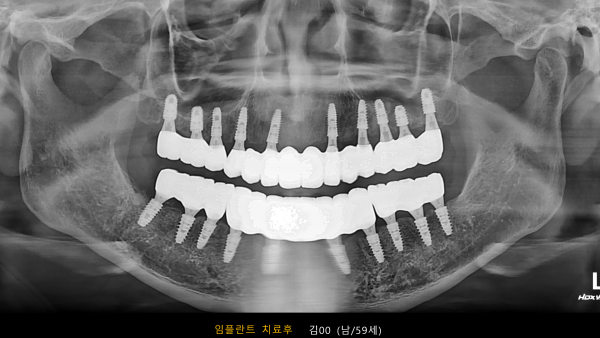

고난도 센터 | 남) 59세